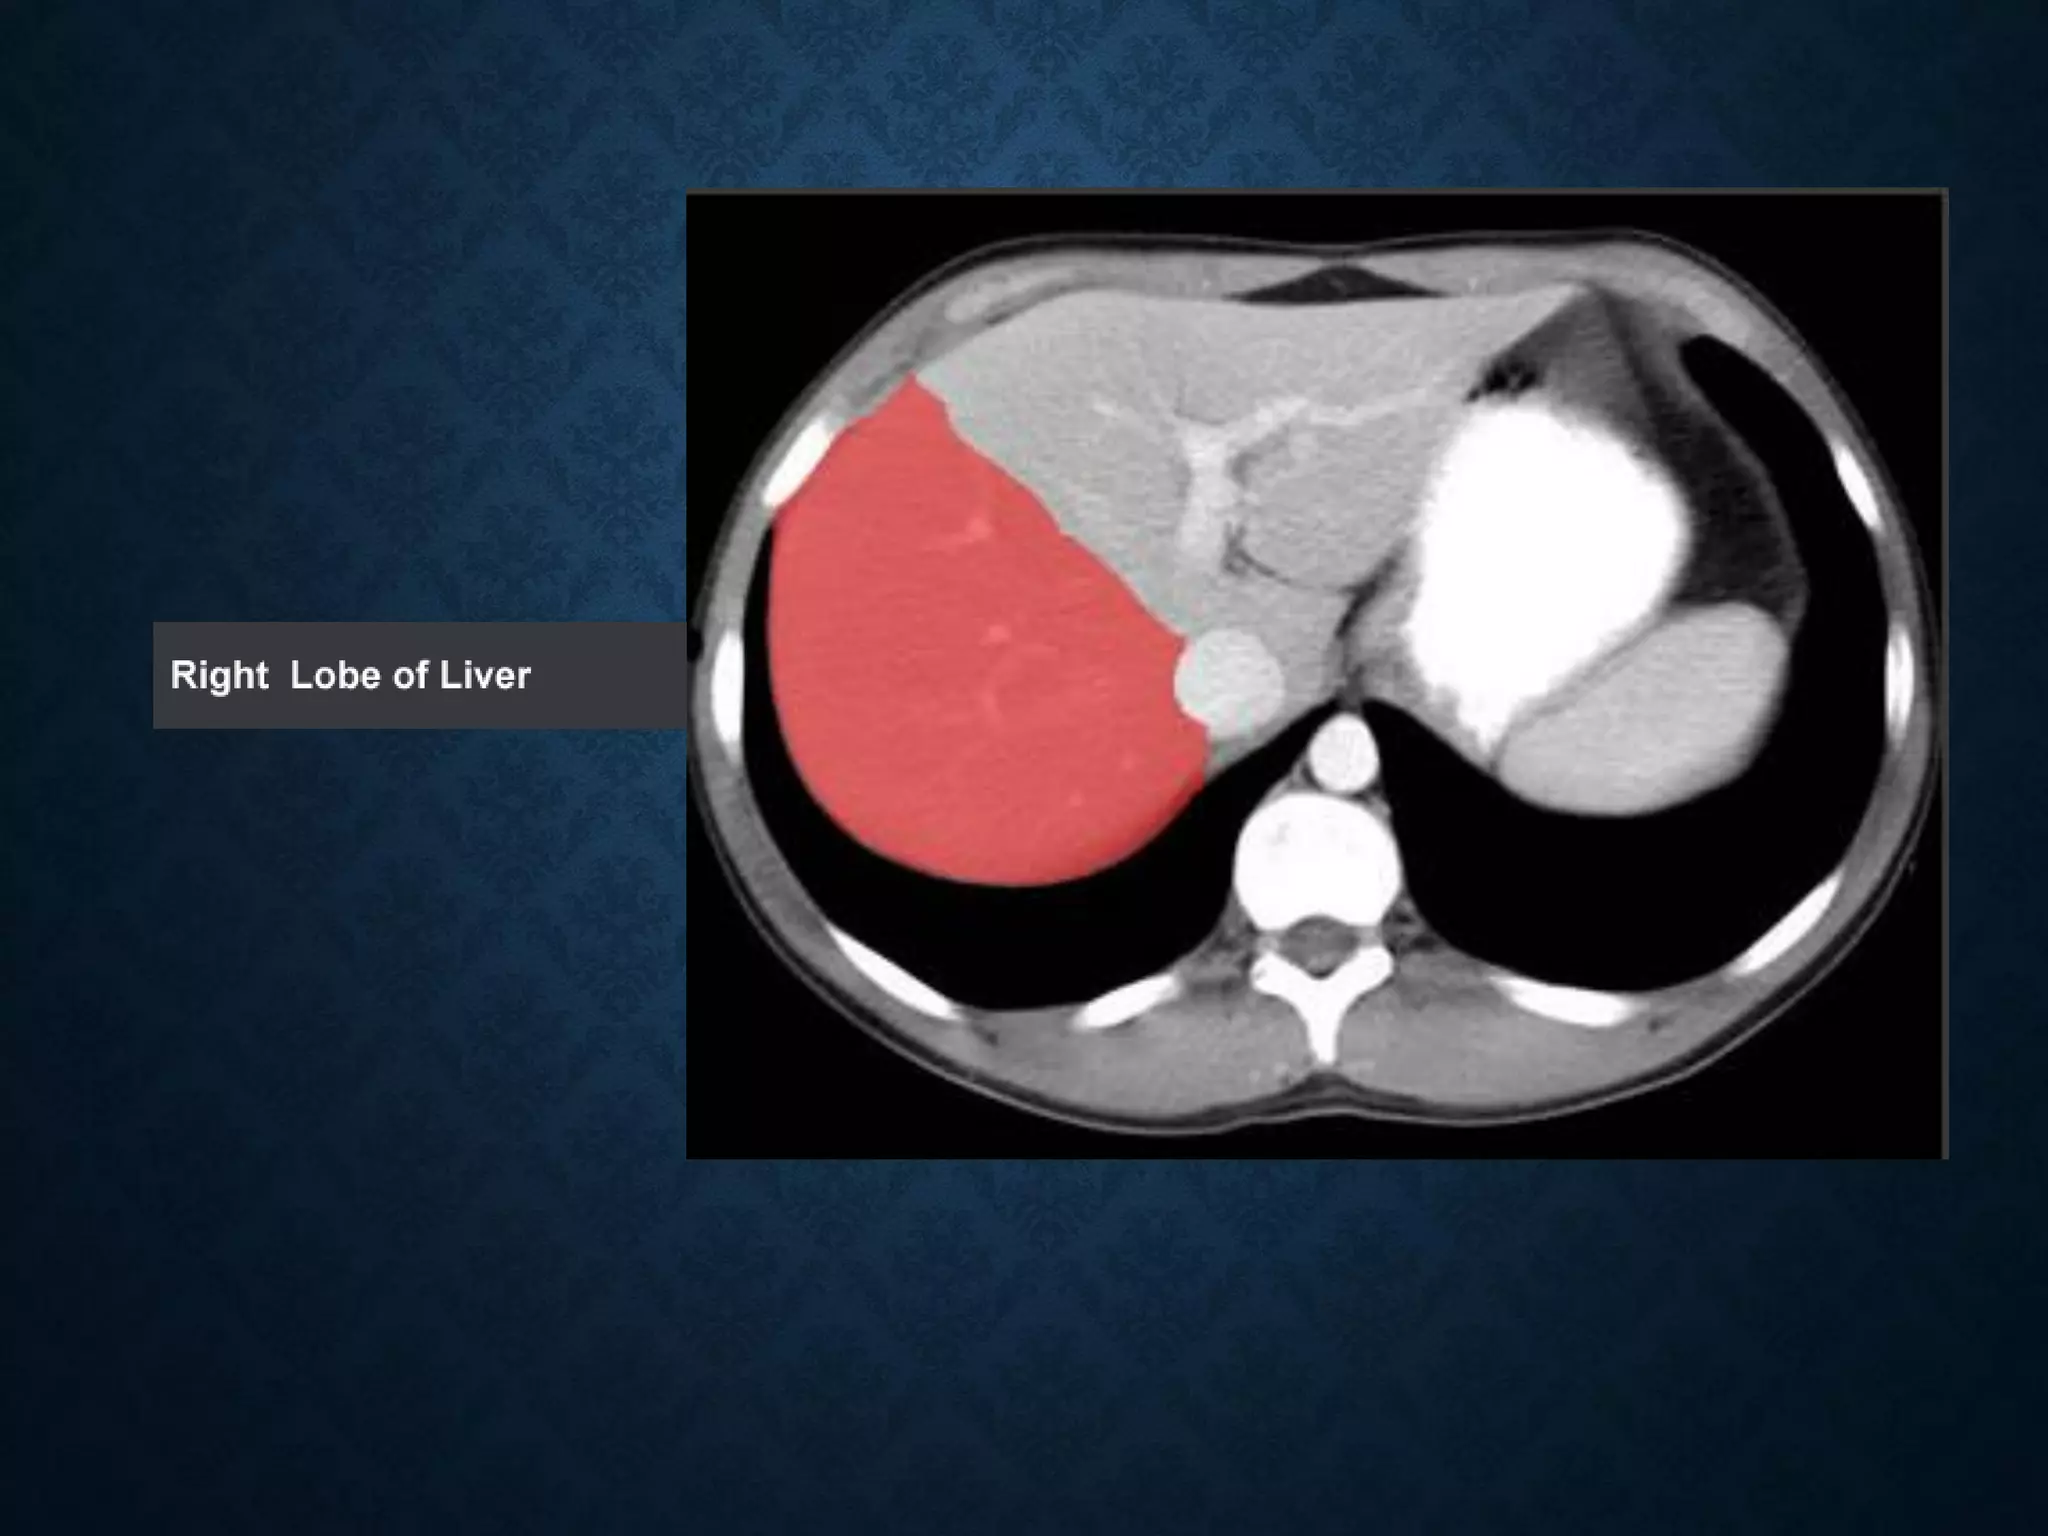

Identify the following structures in the body CT to the right. To view the location of the structure in the image click on

the label at the left and the structure will be indicated in the image. Abdominal CT scans typically begin just above

the diaphragm, so the first slice you see is of the lower chest.